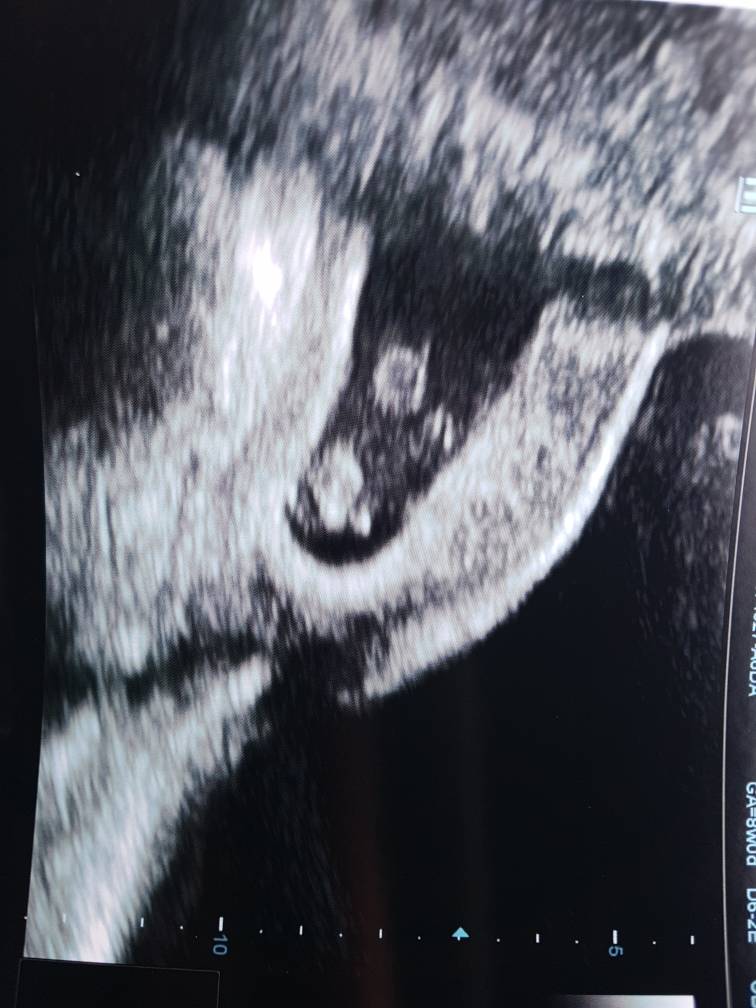

Ale super! Gratulacje! To który dokładnie tydzień pokazuje USG?Hej dziewczyny my juz po wizycieŻabka rośnie, serduszko 173 uderzenia na minute I mierzy juz 1.4cm

BuziakiZobacz załącznik 872765Zobacz załącznik 872766

Dzis jest 8tyg 0d, wg usg 7tyg 6d![]()